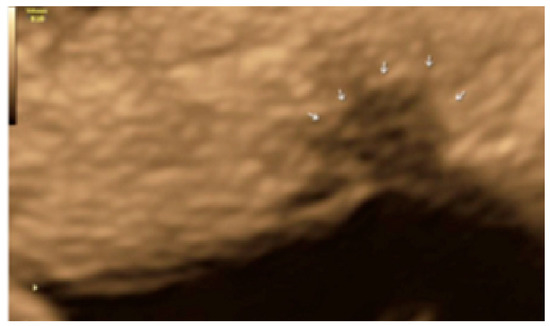

- The presence of hyperechoic foci (we called this a “pearl”).

- The presence of velamentous (filmy) adhesions associated to the lesion (we called this a “veil”).